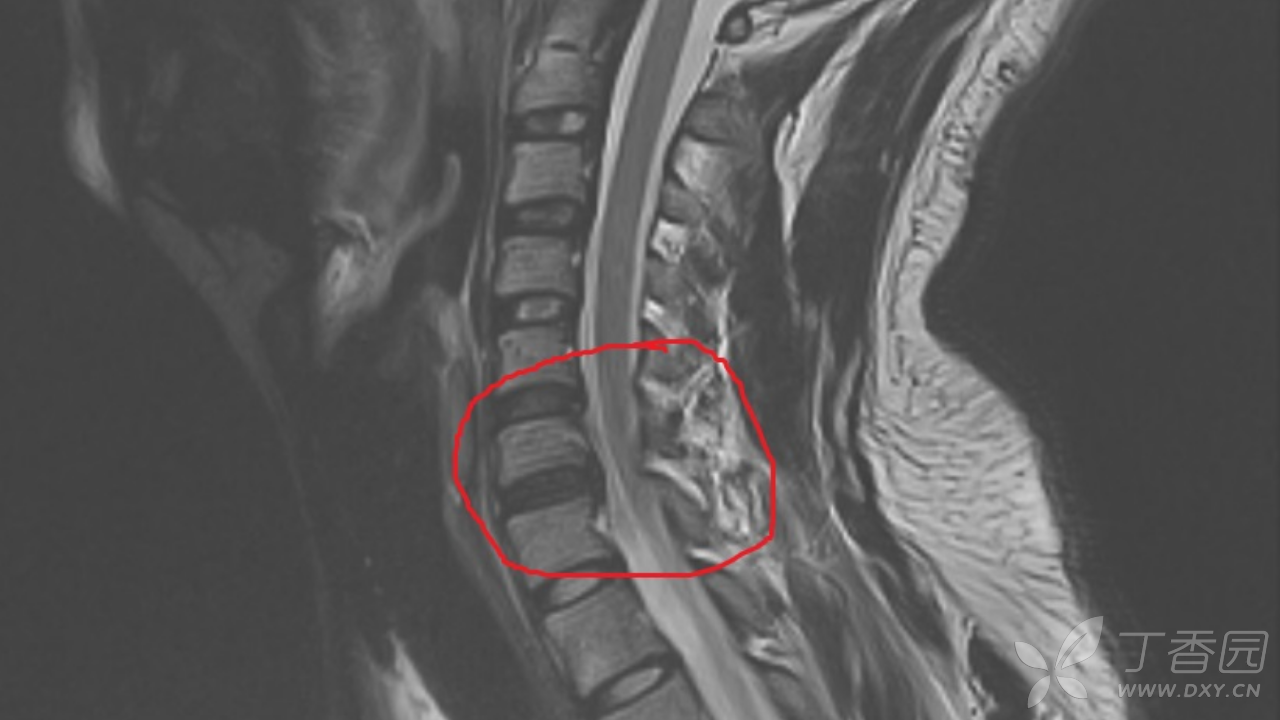

辅助检查:入院查心电图、胸片示正常。腹部+泌尿系B超示脂肪肝。双肾CT示:右肾小结石。附见:L5椎体I°滑脱,双侧椎弓峡部裂,隐裂。颈椎MRI示:2023-01-18 颈椎磁共振平扫(1.5T),颈椎退行性改变:骨质增生;黄韧带稍增厚。椎间盘变性伴C3/4-C6/7椎间盘不同程度膨、突出,双侧神经根受压,椎管稍狭窄,伴颈髓略受压,C4-6左侧神经根T2WI信号稍增高,结合临床。2023-01-18 左肩关节磁共振平扫(1.5),1、左肱骨头关节面下少许骨损伤。2、左侧肩袖前上份损伤,冈上肌、肩胛下肌腱损伤,伴肩袖周围渗出。3、左肩关节肱二头肌长头盂唇复合体(SLAP)损伤可能,结合临床。4、左肩关节下关节囊增厚,考虑慢性损伤可能。5、左三角肌下滑囊及喙突下囊少许积液。6、左肩锁关节炎?。2023-01-17 胸部正侧位,两肺、心膈未见异常。

临床诊断: 疾病诊断:1.颈部脊髓损伤(左侧C4)2.左臂丛神经损伤3.左肩袖损伤4.左肾结石。功能诊断:1.左上肢运动障碍2.颈部、左肩部及上肢疼痛3.日常生活大部分自理